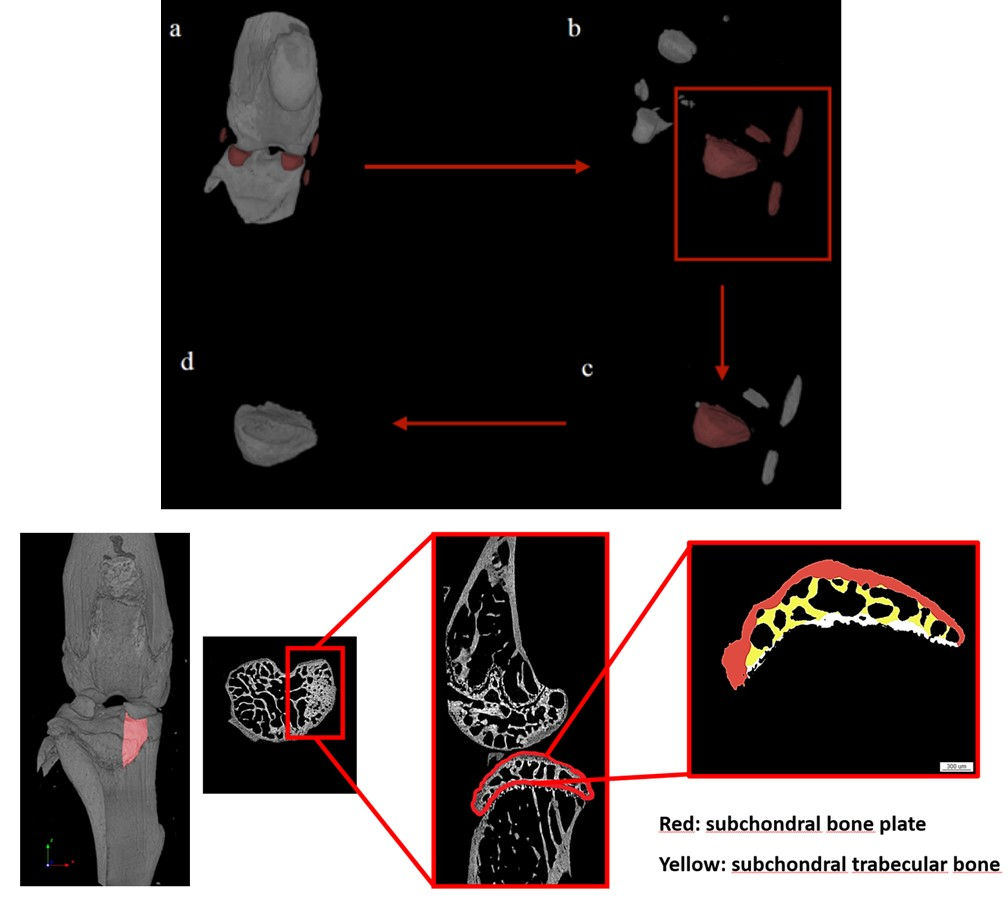

骨关节炎研究方向

半月板扰动诱导的骨性关节炎模型分别展示假手术组、右单侧和双侧造模组可视图,量化统计图分别为内侧半月板体积、软骨下松骨厚度、软骨下骨厚度。[12]

骨性关节炎小鼠模型(Ex vivo)-体积、结构性参数

小鼠交叉韧带横断术(ACLT)骨性关节炎。a. 骨性关节炎模型3D重建图,手术组软骨下骨大面积增生、磨损。b. 内侧半月板抓取示意图 c. 股骨软骨下骨松质骨横截面,手术组骨体积减少。d. 软骨下松骨结构性参数以及胫骨平面各项参数。

骨性关节炎模型造模手段通常有交叉韧带横断术(ACLT)和内侧半月板扰动(DMM)二者的评判标准和分析角度几乎一致,如胫、股骨软骨下松骨的结构性参数以及胫骨平面的厚度和孔隙度等,如果更关注软骨还可以进行离体组织造影来分析软骨。